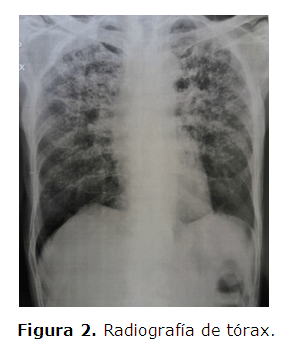

Se inicia tratamiento con trimetroprin-sulfametoxazol. Después de 8 días mejora el cuadro respiratorio y es egresado con trimetroprin-sulfametoxazol oral 480 mg 2 comprimidos cada 12 horas y dexametasona 4 mg cada 6 horas. Se toma muestra de suero para serología Blastomicosis-anticuerpos paracoccidioidomicosis con resultado no reactivo y se realiza otra radiografía de tórax (Figura 2).